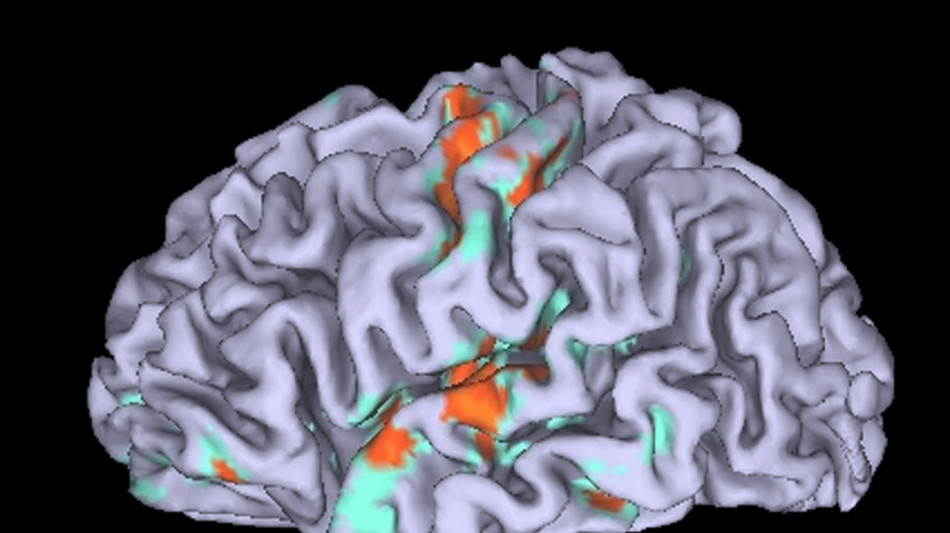

Il nostro cervello divide la giornata in capitoli, voltando pagina non quando cambia il contesto in cui ci troviamo, bensì quando accade qualcosa di importante in base alle aspettative e agli interessi su cui siamo focalizzati. Lo hanno scoperto gli psicologi della Columbia University grazie a uno studio pubblicato sulla rivista Current Biology. "Volevamo mettere in discussione la teoria secondo cui i repentini cambiamenti dell'attività cerebrale che segnano l'inizio di un nuovo capitolo della nostra giornata sono causati solo da repentini cambiamenti nel mondo, insomma che il cervello non sta realmente facendo nulla di interessante quando crea nuovi capitoli, sta solo rispondendo passivamente a un cambiamento negli input sensoriali", spiega il coordinatore dello studio Christopher Baldassano, professore associato di psicologia alla Columbia University. "La nostra ricerca ha scoperto che non è così: il cervello, in realtà, organizza attivamente le nostre esperienze di vita in blocchi che sono significativi per noi". Per capire come il cervello segna il confine tra gli eventi per registrarli come capitoli distinti della giornata, i ricercatori hanno misurato l'attività cerebrale di alcuni volontari sottoponendoli a risonanza magnetica funzionale mentre ascoltavano 16 audio in cui venivano raccontate quattro storie (la rottura di una coppia, una proposta di matrimonio, un accordo commerciale e un bell'incontro) in quattro ambienti diversi (un aeroporto, un ristorante, un supermercato e un auditorium). I risultati dimostrano che il cervello divide l'esperienza in singoli eventi in base a quello a cui si presta attenzione, come se seguisse una sorta di copione interiore basato sulle esperienze passate e sulle aspettative. Ascoltando per esempio la storia della proposta di matrimonio al ristorante, la corteccia prefrontale dei volontari ha organizzato la storia in capitoli relativi alla proposta di matrimonio in vista del fatidico sì, mentre lo ha fatto in modo del tutto diverso quando invece veniva chiesto ai partecipanti di focalizzarsi su quello che la coppia mangiava al ristorante: in quest'ultimo caso, momenti come quello dell'ordinazione dei piatti sono diventati capitoli cruciali della storia.